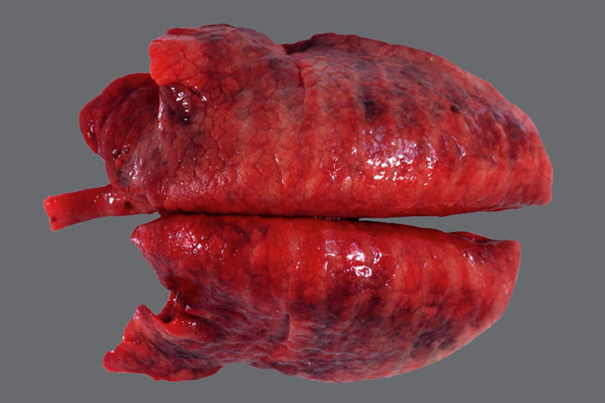

Schwein, Lunge: hochgradige, akute bis subakute, multifokale, fibrinöse Pleuropneumonie

- zufällige Verteilung der der Parenchym- und Pleuraveränderungen:

- in Spitzen- und Hauptlappen finden sich multiple landkartenähnliche Herde von roter bis dunkelroter Farbe und verfestigter Konsistenz

- multifokale, gelblichgraue Beläge auf der Pleura (= Fibrin), welche überwiegend mit den Herden des Parenchyms assoziiert sind

- Interstitien teilweise verbreitert

Ätiologie

- meistens, jedoch nicht ausschließlich, bakterielle Sekundär-Erreger nach primärer Virusinfektion

Erreger-Spektrum:

- vor allem gramnegative Bakterien (HAP-Gruppe), die Erreger besitzen Endotoxin (Lipopolysaccharid) und

bilden außerdem vielfach hochpotente Exotoxine (z.B. Apx-Toxine von Actinobacillus pleuropneumoniae)

H aemophilus (Glässerella) sp.

A ctinobacillus sp. (A. pleuropneumoniae = primäre Infektion beim Sw., außerdem A. suis und A. equuli)

P asteurella sp. (Mannheimia haemolytica (Rd.), P. multocida)

- außerdem aus der Familie der Pasteurellaceae: Histophilus somni (Rd.) und Bibersteinia trehalosi (Wdk.)

- Mycoplasmen (M. mycoides subsp. mycoides Small Colony Type, der Erreger der (anzeigepflichtigen!)

Lungenseuche des Rindes) und Mycoplasma bovis

- Pilze (Schimmelpilze)

Hintergrundwissen/ Infektionsweg/ Pathogenese

- die fibrinöse Pneumonie ist eine Form der Bronchopneumonie:

- aerogene Infektion > Bronchiolitis > peribronchioläre und endobronchioläre Fortleitung:

a) peribronchiolär > entlang der interstitiellen Lymphgefäße > Thrombose der Lymphgefäße > kein

Lymphabfluß (Gewebe ertrinkt und „stirbt“ im Ödem) > auf diesem Weg wird auch die Pleura erreicht

(Pleuropneumonie)

b) endobronchiolär > Alveolen füllen sich mit Entzündungsprodukten und Zellen an (Ödem, Fibrin, PMN,

Mø)

- makroskopisch typisch ist die kranioventrale Konsolidierung des Parenchyms; eine Ausnahme stellt die porzine

Pleuropneumonie* (APP) dar, weil die kaudalen Lungenlappen oft am stärksten betroffen sind

* meistens geht die fibrinöse Pneumonie mit einer fibrinösen Pleuritis einher > fibrinöse Pleuropneumonie

- neben der fibrinösen Komponente können auch Hämorrhagien und Nekrose (Sw: helle, landkartenähnliche und

trockene Herde in der gesamten Lunge) vorkommen

- die typische bunte Marmorierung des Parenchyms des Rindes entspricht dem klassischen (protrahierten) Ablauf in

vier Stadien:

1) Anschoppung

2) rote Hepatisation (leberähnlich, hepar = Leber)

3) graue Hepatisation

4) Organisation (Karnifikation)

- Komplikationen der fibrinösen (Pleuro-)Pneumonie: Sequester (v.a. Mykoplasmeninfektionen), Pleuraadhäsionen,

Abszesse bzw. Pleuraempyeme